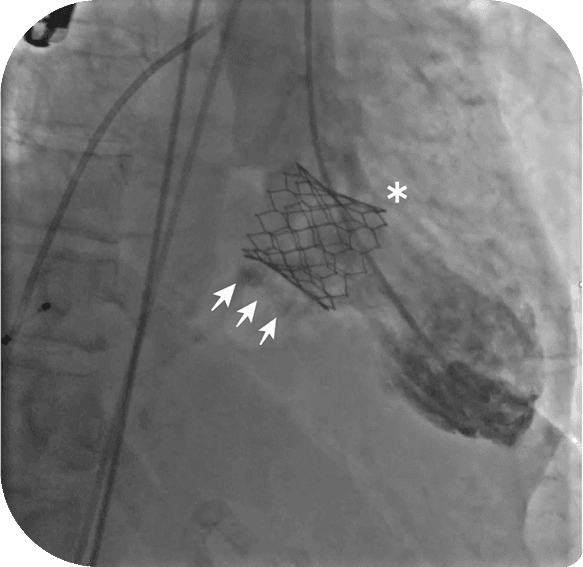

TMVR procedure performed via catheter approach through the femoral vein, often under conscious sedation

When this happens, Valve-in-Valve TMVR offers a minimally invasive alternative to repeat open-heart surgery. Instead of replacing the old valve entirely, a new transcatheter valve is placed inside the existing one.

Real-time 3D echocardiography and cardiac CT help in accurate valve sizing and positioning.